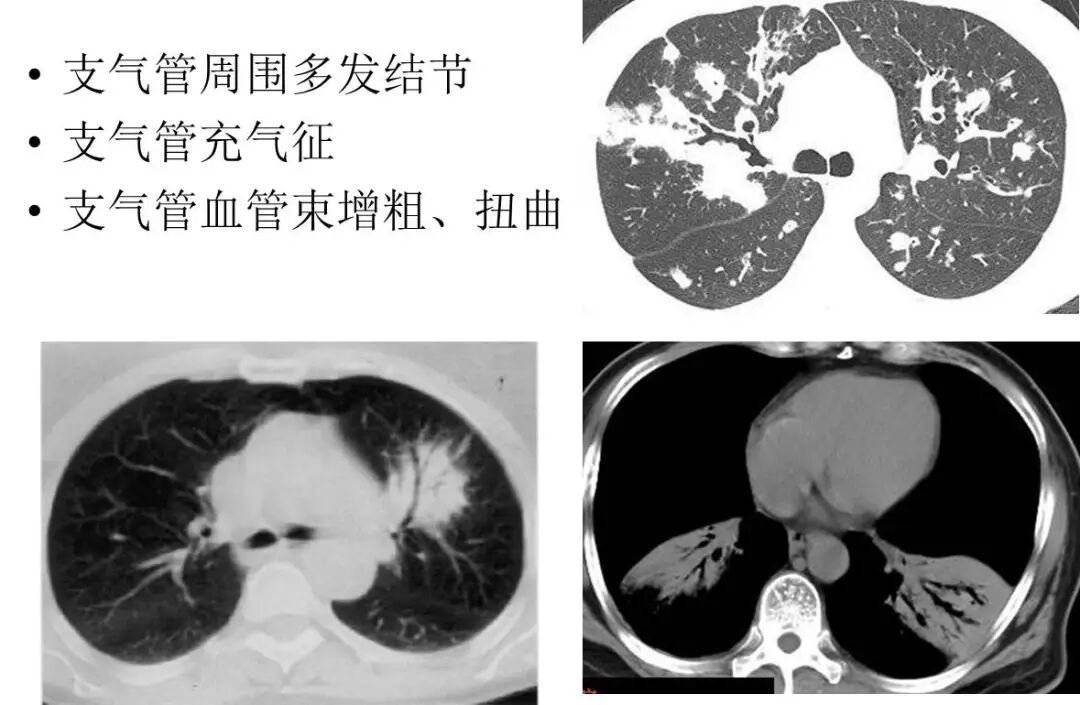

▶结节肿块型

▶肺炎肺泡型

▶支气管血管淋巴管型(间质型)

MALT 的支气管扩张并无支气管管壁的破坏。由于淋巴瘤组织浸润导致肺泡塌陷,支气管周围实质破坏造成的,这类支气管扩张在肿瘤治疗后有时可消失。

肺粘膜相关淋巴瘤

结节、肿块,边缘模糊

充气支气管粗大、扭曲

▼伴有空气支气管征充气的支气管粗大、扭曲;